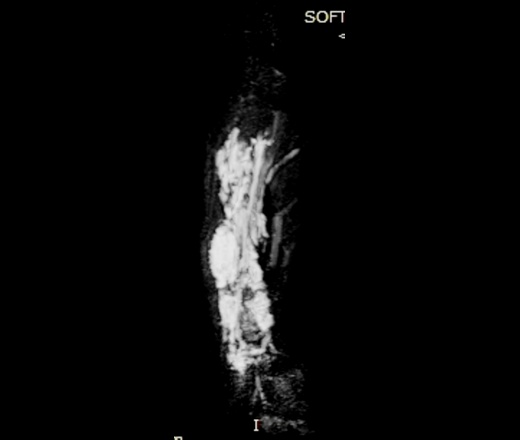

При контролях в динамике - мягкотканный компонент с наличием округлых теней.

УЗИ - мягкотканный компонент с наличием кровотока.

МРТ - гемангиома мягких тканей.

Округлые плотные тени - флеболиты.